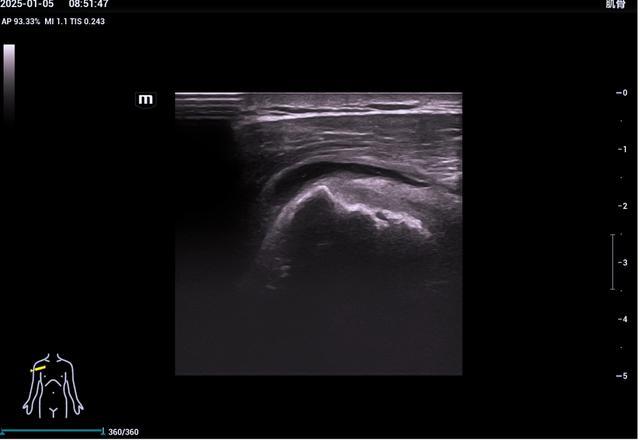

1、肩关节超声检查

肩袖损伤、肌腱病、粘连性关节囊炎(肩周炎)、肱二头肌长头腱肌腱炎及脱位、肱二头肌断裂、肩锁关节炎等。

▲三角肌下滑囊积液

▲冈上肌肌腱撕裂(部分宽度全厚度撕裂)